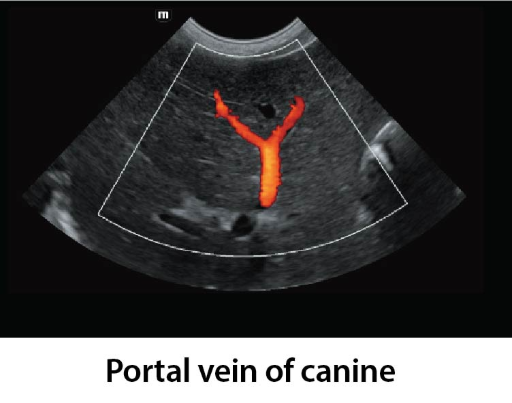

Клинични снимки

Clinical Images